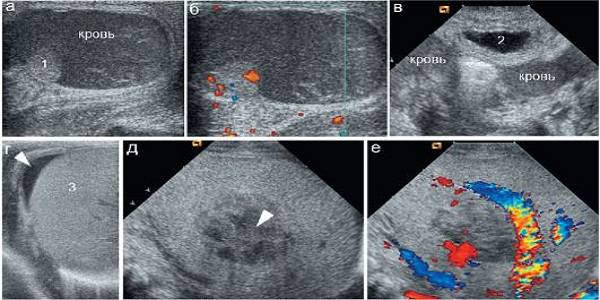

Анэхогенное образование — это жидкость (кровь), на экране она не отображается.

Гипоэхогенное образование — на экране выглядит как темное пятно, отображается достаточно плохо, чаще всего это киста печени. Она имеет округлую форму, может в структуре иметь перегородки.

Также такие образования могут быть в виде аневризмы печеночной артерии, эхиноккоковой кисты (ее стенки эхогенные, а внутри кальценаты), киста, которая соединилась с воротной веной. А также к таким образованиям относятся сгустки крови, гной, опухоли и т.д.

- Анэхогенная структура представляет собой фактически чёрное пятно, характерна для жидкостных органов, например, мочевого и желчного пузырей. Также может быть проявлением патологического процесса, такого как абсцесс или киста органа.